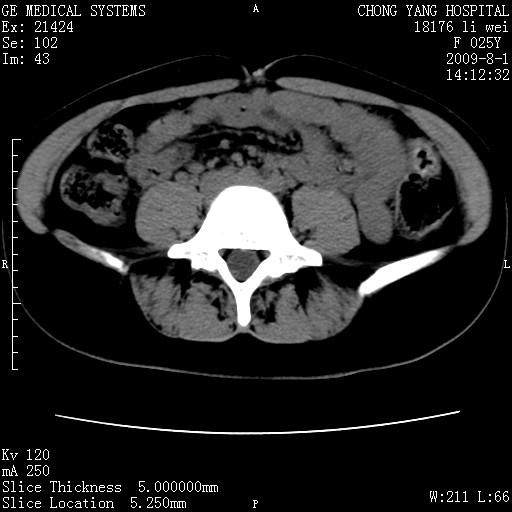

以下是引用pujunzhi在2009-8-1 20:23:00的发言:[br]胸椎旁及背部肌间良性病变,范围广,边界清,沿肌间生长,考虑淋巴管瘤、血管瘤,建议增强扫描。

以下是引用拾荒者在2009-12-30 21:45:00的发言:[br]ct21383:神经纤维瘤病( nf) [br] [br] 神经纤维瘤病。四肢都有,影响美观,四肢上的手术了。[br] [br] [br]谢谢!